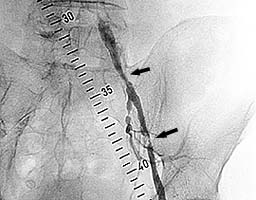

Пациент с жалобами на перемежающуюся хромоту,

боли возникают после ходьбы 20м.

На ангиограмме - стенозы наружной

подвздошной и общей бедренной артерий (рис.4).

Рис. 4 |